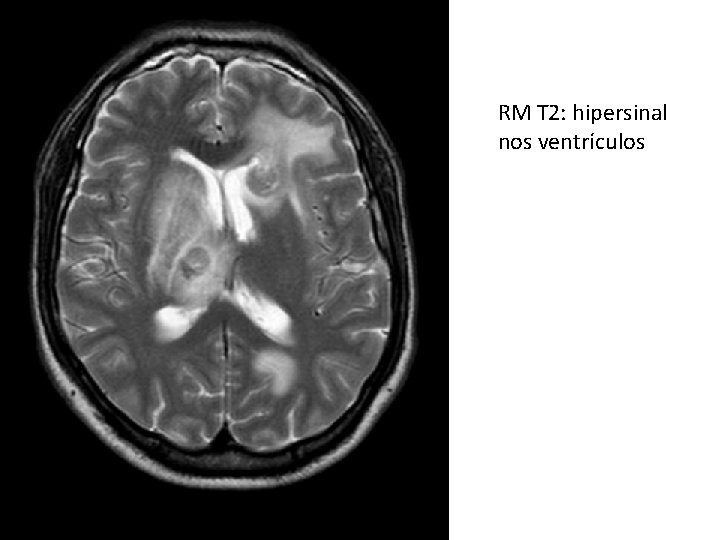

RM T 2: hipersinal nos ventrículos

FLAIR= sequencia ponderada em T 2 com inversão do sinal do liquor: LCR fica preto, mas o que é edema permanece branco (qq liquido q não for LCR fica branco).